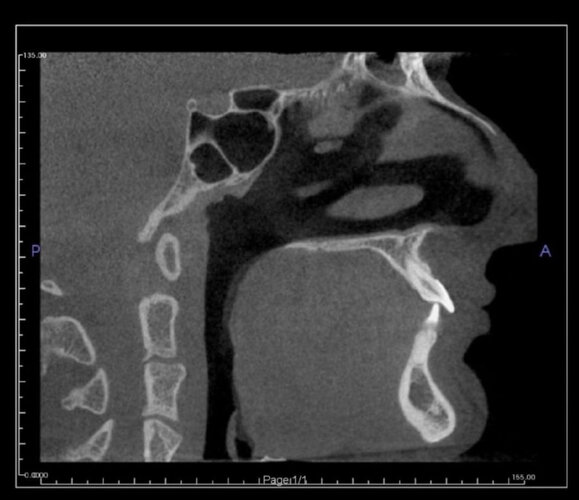

Needing serious advice on what would best surgeries for myself. I’m currently exploring double jaw surgery and rhinoplasty for my subhuman face.

My maxillofacial surgeon has suggested a segmental upper jaw, lower jaw and genioplasty; will cost 12k but I have to wait a year for insurance to cover the hospital side which is 30k… I’m not interested in going overseas for this either.